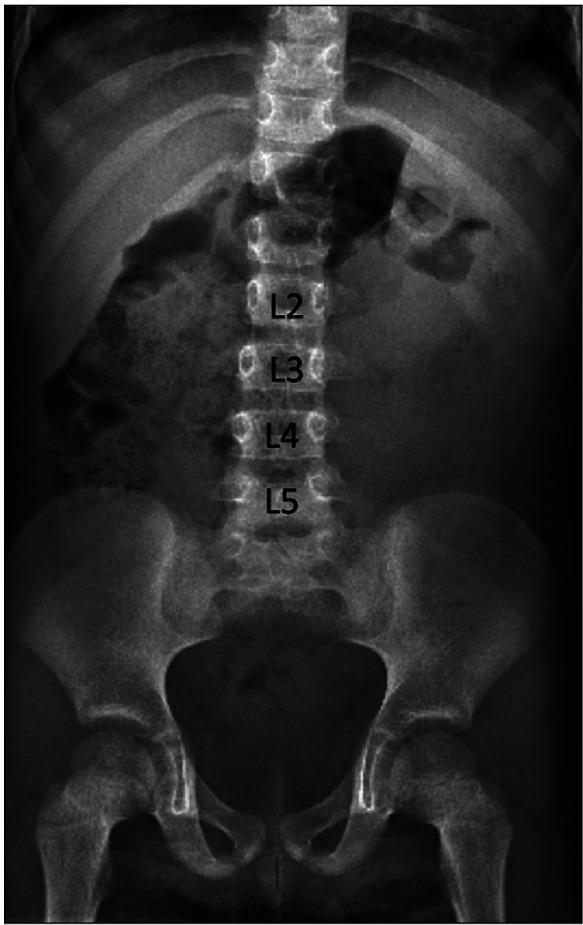

尾椎退化综合征与盆腔肾:病例报告

Caudal regression syndrome and a pelvic kidney: case report.

Caudal regression syndrome (CRS) is a rare congenital variation. A high incidence of renal and genitourinary malformations has been observed in patients with CRS, with the most common being neurogenic bladder and renal agenesis. We report a rare case report documenting both CRS and a pelvic kidney found during a diagnostic magnetic resonance imaging. Although renal anatomy variants are found in patients with CRS, a pelvic kidney is normally not part of the constellation of findings in this malformation. As seen in our patient, a pelvic kidney should be considered in patients suspected of having CRS.

摘要

尾椎退化综合征(CRS)是一种罕见的先天性变异。在CRS患者中观察到肾脏和泌尿生殖系统畸形的发生率很高,最常见的是神经源性膀胱和肾缺如。我们报告了一例罕见病例,记录了在诊断性磁共振成像中发现的CRS和盆腔肾。虽然在CRS患者中发现了肾脏解剖变异,但盆腔肾通常不是这种畸形的一系列表现的一部分。如我们的患者所见,对于疑似患有CRS的患者应考虑盆腔肾的存在。